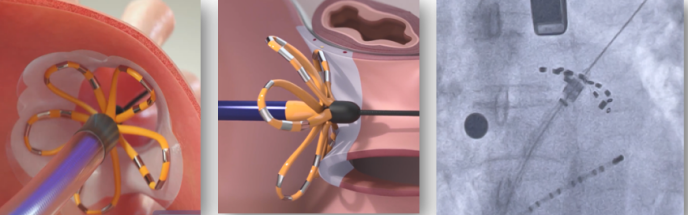

脉冲电场消融是一种利用高强度、短时程电场作用于细胞膜,诱导细胞膜不可逆电穿孔(IRE),从而实现靶向消融的技术。其核心原理在于不同组织对电场的敏感性差异:心肌细胞膜电位较低,易发生电穿孔;而血管、神经和食道等结构则相对耐受,因此可减少非目标组织损伤的风险。多项前瞻性研究表明,PFA在房颤消融中具有较高的成功率和较低的并发症发生率,尤其适用于合并心功能不全或高危解剖结构患者[1]。然而,任何新技术均需建立完善的围手术期管理体系,以确保患者安全并优化疗效。

图1、左上肺静脉放电消融示意图